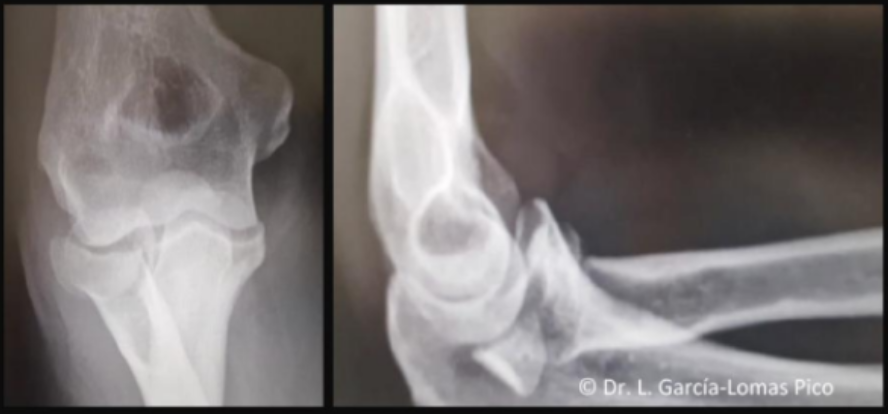

Tipo de fractura en la clasificacion de Mayo

1a (no desplazada, no conminutada)

2a (Desplazada estable, no conminutada)

3b (Desplazada inestable (por la luxacion) y conminutada)